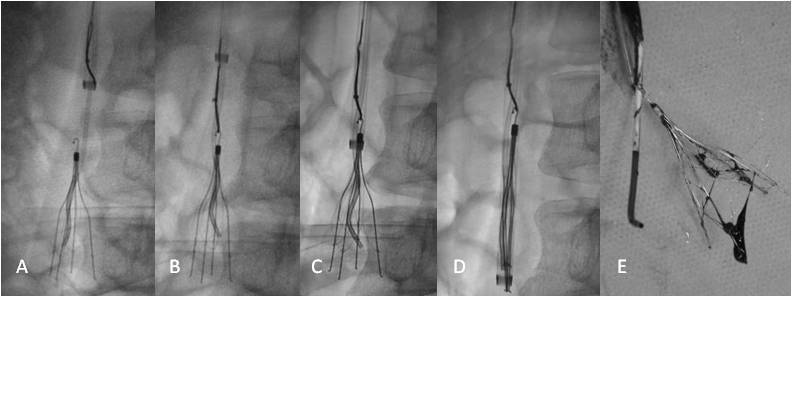

疑难性下腔静脉滤器取出的技巧及策略 - 好大夫

844x509 - 32KB - JPEG